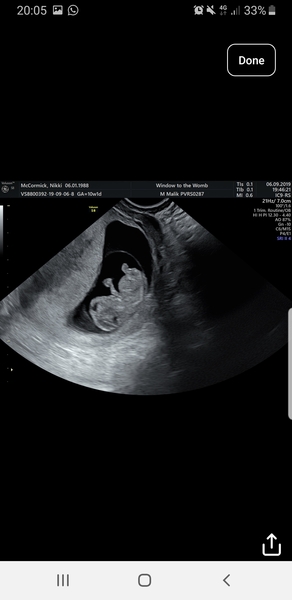

Had my scan it's so surreal. Feel much more relaxed for my holiday in 2 weeks. EDD 7th april 2020

@nikdan123 wow your scab is so clear. Was it internal or external? You’re due 3 days after me. I had external at epau last Monday due to bleeding and it was no where near as clear as that!

Scan not scab!! Blush

@Whatelsecouldibecalled yes it was internal. She tried external but wasnt very clear. Theres a pic of external one. I couldnt believe how clear it was and how much you could see for just 9 weeks 3 days. Makes it so real and exciting. Got my official first scan on 30th september. Thay was a private one for reassurance. Best £50 ever spent. Grin

@nikdan123 Wow that scan is amazing! I feel so far behind you, my booking in appointment is the day you have your 12 week scan!